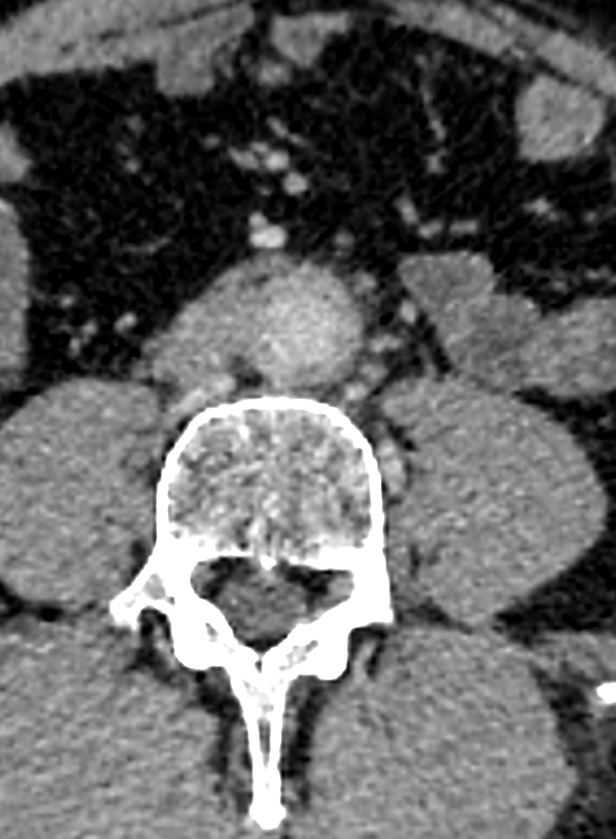

A aortite é a inflamação da parede da aorta, podendo se estender para ramos como as artérias ilíacas comuns. Essa condição pode causar espessamento vascular e alterações no fluxo sanguíneo, muitas vezes detectadas por exames de imagem.

Baseia-se na correlação clínica e laboratorial associada à imagem vascular. A angio-TC contrastada é um dos principais métodos de avaliação, sendo referência prática na investigação e acompanhamento.

Imagem 2